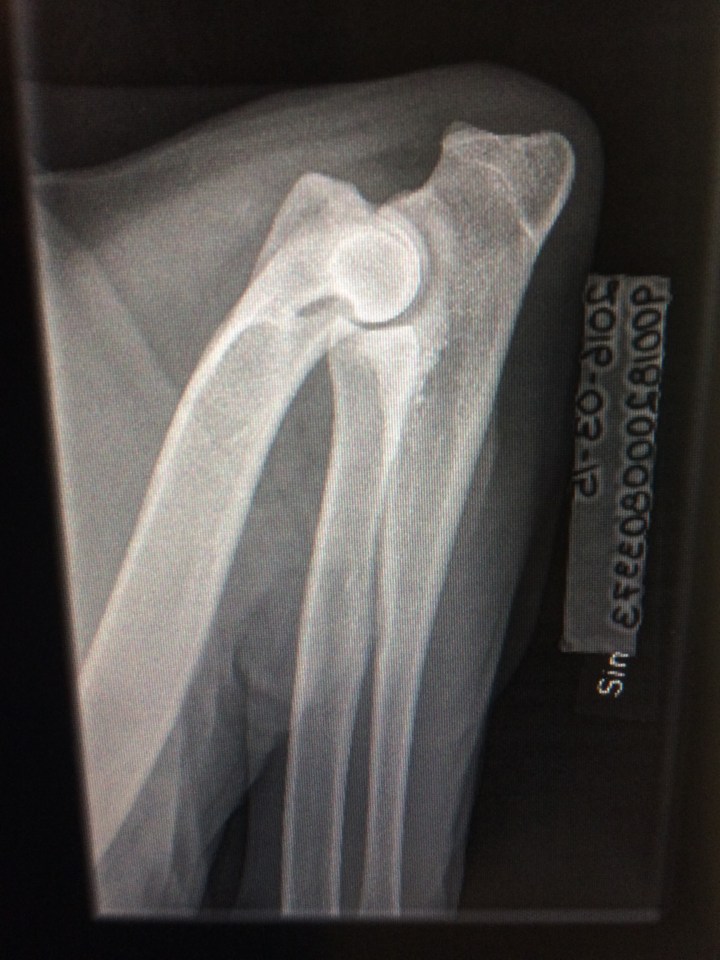

IMG_5474 ← Föregående Vänster armbåge, ED: 1 Dela detta: Dela på Facebook (Öppnas i ett nytt fönster) Facebook Dela på Pinterest (Öppnas i ett nytt fönster) Pinterest Dela på Instagram (Öppnas i ett nytt fönster) Instagram Gilla Laddar in …